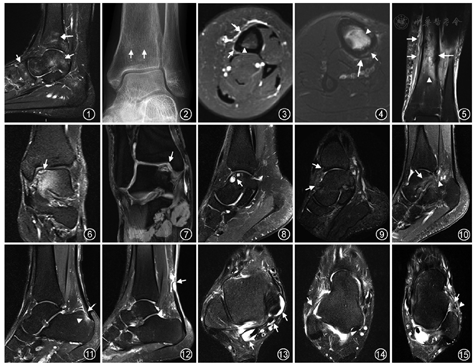

骨损伤主要表现为骨髓水肿及应力性骨折。骨髓水肿通常无症状,在运动量较大、剧烈运动后或由于步态及负重改变的个体中,可出现踝关节骨髓水肿灶[7,8]。其发生机制目前尚不清楚,有学者认为是一定的外力作用于骨质后导致骨小梁的微骨折;也有认为是骨髓组织的生理反应,属于可逆性改变[8,9]。所以,骨髓水肿的出现可与创伤的严重性不对应。MRI短时反转恢复(short time inversion recovery,STIR)或脂肪抑制(fat suppression,fs)-T2WI序列对其检测最为敏感,表现为斑片状高信号(图1)。

目前,MRI是诊断应力性骨折最敏感和特异的影像方法[11],在踝关节出现症状后1~2 d即可有阳性表现。常规X线检查阳性率不高,特别是在骨折早期,X线检查常无异常发现;一般在出现临床症状2~3周后骨折部位可见骨质硬化区(图2[13])。踝关节应力性骨折好发于胫骨远端,MRI典型表现为T1WI和T2WI上线样低信号影及邻近的骨髓及软组织水肿。胫骨远端应力性骨折的MRI评估最常用的是Fredericson分级:1级,仅表现为fs-T2WI上骨膜水肿,骨髓信号仍正常;2级,fs-T2WI上除骨膜水肿外,还伴有轻度的骨髓水肿(图3[13]);3级,T1WI和fs-T2WI上均可见明显的骨髓水肿,以及骨膜水肿;4级,特征表现为T1WI和fs-T2WI上清晰的骨折线、明显的骨髓水肿及骨膜水肿[15]。Kijowski等[16]将4级损伤细分为4a级和4b级,其中4a级损伤表现为骨皮质局部信号异常,未出现骨折线(图4[13]),而4b级损伤存在线样骨皮质信号异常(图5[13])。同时,Kijowski等[16]结合恢复活动时间对这些分级进行了扩展,强调了1级、2~4a级损伤的恢复活动时间分别为2~3周、6~7周,而4b级损伤的恢复活动时间为9~10周。这说明早期发现这些损伤对及时治疗及指导休息和训练的重要性,并可能因此而延长运动员的职业生涯[16,17]。

MRI可早期发现OLT[18],其灵敏度和特异度均为96%[22],表现为距骨穹隆面软骨变薄、增厚或软骨断裂等;损伤区软骨可见分离或移位的骨皮质、软骨下骨髓水肿及软骨下骨囊肿;而且,软骨下骨髓水肿的范围与软骨退变程度有关[24]。目前,临床上使用的MRI分期大多是在X线分型的基础上发展而来,使用最多的是Hepple分期[25]:1期,仅关节软骨损伤;2a期,关节软骨损伤伴软骨下骨骨折及骨髓水肿(图6);2b期,关节软骨损伤伴软骨下骨骨折,但无骨髓水肿;3期,骨软骨片与距骨体分离,但无移位(图7);4期,骨软骨片与距骨体分离、移位;5期,关节软骨下骨囊肿形成(图8)。准确掌握这些分期有助于指导治疗。

前外踝撞击综合症多见于青壮年男性,尤其是运动员,病变发生在外侧距腓关节围成的外侧沟内。MRI主要表现为前外侧沟内异常组织填充,可分为瘢痕组织、滑膜增生组织及韧带撕裂后填充。滑膜炎在轴面fs-T2WI表现为前外侧沟区结节状等、高信号影,出现此表现时应密切观察邻近的韧带,尤其是距腓前韧带和胫腓前下韧带,以了解其创伤后的变化。而且,滑膜炎可能会随着时间的推移演变为前外侧沟内信号均匀的"半月板样"结构[27,28]。纤维瘢痕组织或前外侧沟内"半月板样"结构在轴位fs-T2WI上显示最好,呈低至等信号改变。

前踝撞击综合症又称足球踝,通常为骨性撞击。X线表现为胫骨前下缘与距骨颈部前上缘鸟嘴样骨刺形成,但需在无胫距关节间隙变窄和胫距角减小的情况下才有助于诊断[29]。MRI能对相关的软骨、滑膜、韧带及肌腱等软组织病变进行评估(图9)。其中滑膜炎在矢状位fs-T2WI上观察较佳,表现为前隐窝内高信号影。

后踝撞击综合征常见于频繁跖曲的运动员,以骨性撞击多见,X线可显示距骨后突(Stieda突)的过度突出或距骨后三角骨的存在及损伤。MRI可表现为距骨后部、距后三角骨内骨髓水肿及距骨后缘关节囊、韧带增厚(图10),可伴有

长屈肌腱鞘炎及邻近滑膜不同程度的炎性增生[29]。

跟腱损伤是运动员最常见的损伤,常见于跑步、足球及跳跃运动中[4]。小腿肌群过度运动是跟腱病变的主要原因。MRI上,跟腱损伤表现为跟腱局灶性或梭形增粗、信号增高、跟骨的跟腱附着处骨髓水肿等(图11);轴位fs-质子密度加权像(protein density weighted imaging,PDWI)示跟腱前缘隆突而失去正常前凹的形态。当跟腱发生钙化或骨化时,MRI所有序列均表现为低信号,此时X线或CT检查显示效果更佳。跟腱断裂好发于跟骨附着部上方2~6 cm处,此处血供减少且最细[6]。跟腱部分撕裂的MRI表现为跟腱局部性中断,形态欠规则,撕裂处呈不均匀T1WI低信号、T2WI高信号影。完全撕裂则表现为跟腱断裂、不连续,可见高信号液体填充,跟腱断端挛缩、增粗及信号不均(图12)。但是,传统的MRI序列仅可显示跟腱病变的晚期改变,也无法进行定量测量;目前,可以采用三维超短回波时间序列对跟腱病变进行早期诊断和定量评估[30]。

长屈肌腱、趾长屈肌腱等损伤,在T2WI上可见肌腱内信号增高及周围腱鞘内积液增多(图13)。

韧带损伤是踝关节最常见的运动损伤,由于长期、反复、大运动量的训练和比赛容易导致韧带发生解剖结构和病理改变,以慢性损伤为主。外侧副韧带比内侧三角韧带更易发生损伤,损伤发生率高低依次为距腓前韧带、跟腓韧带、距腓后韧带;且韧带损伤通常为多条韧带同时受累,外侧副韧带损伤时多合并内侧三角韧带部分损伤,而内侧三角韧带单独损伤发生率很低[33]。韧带损伤多以部分损伤为主,完全断裂少见,MRI常表现为韧带内信号异常(图14);损伤韧带形态可不规则,局部或弥漫增粗、变细,甚至呈波浪状改变;韧带断裂则表现为韧带连续性中断,信号增高,边界不清,可伴有周围软组织水肿及积液(图15)。